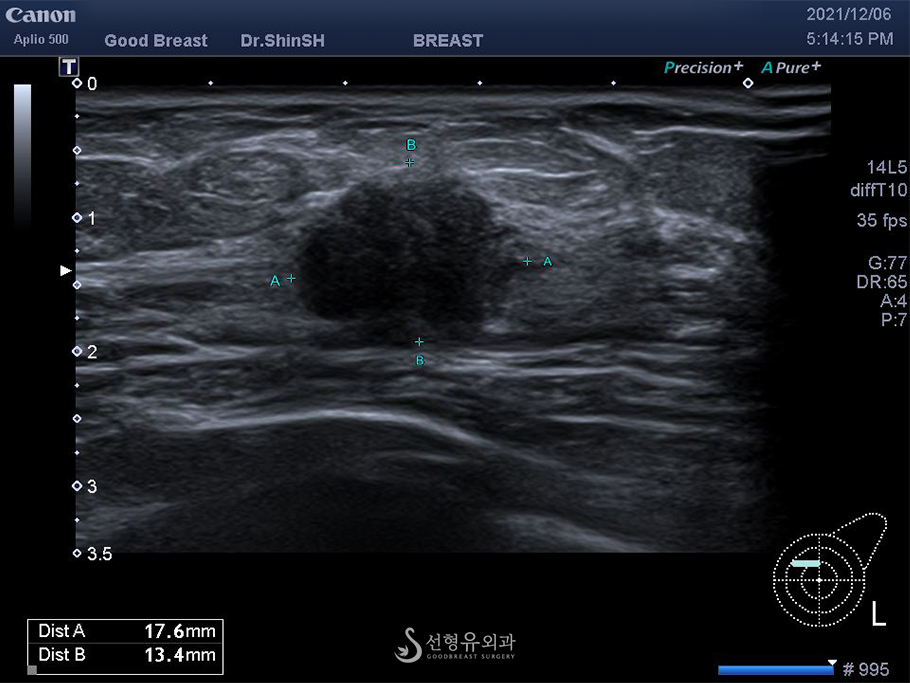

탐침자로 유방을 꼼꼼하게 검사하여 혹을 찾아내고 조직검사 여부를 판단해야 하기 때문에 초음파 기계의 해상도와 검사자에 따라 결과가 달라질 수 있습니다.

과거에는 초음파 영상으로 혹의 크기와 모양 정도만 확인하였지만 최신 초음파 기계장치는 여러 기능이 탑재되어 단단한 정도와 미세석회병변까지 찾아낼 수 있습니다.